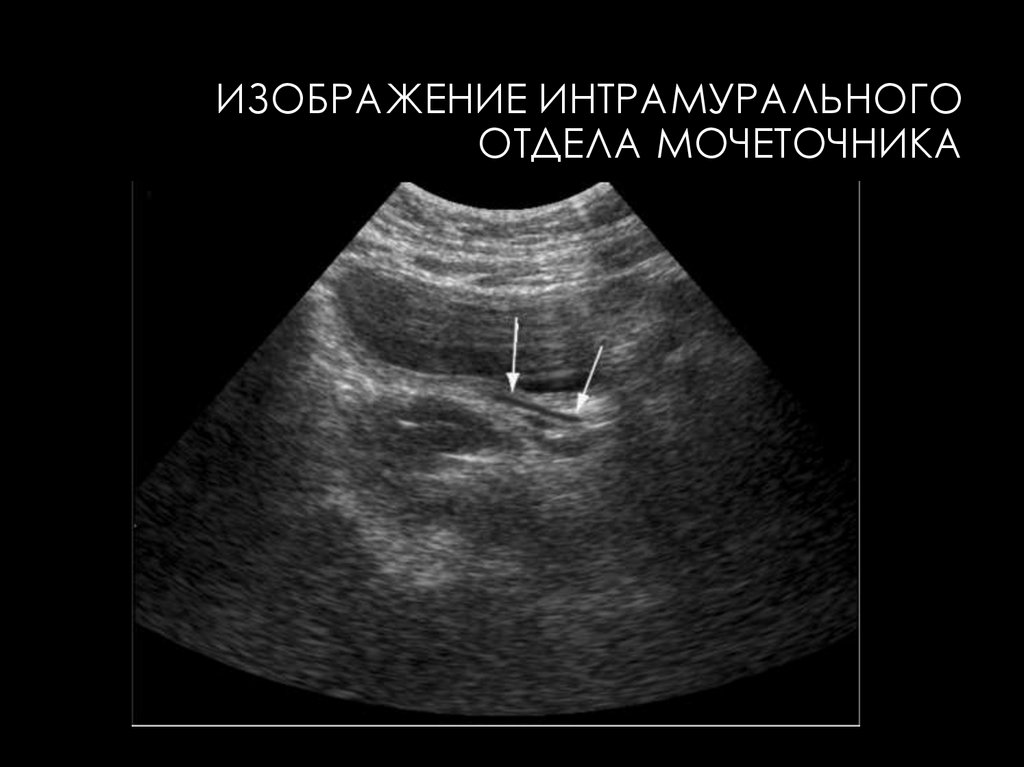

23.

ИЗОБРАЖЕНИЕ ИНТРАМУРАЛЬНОГО

ОТДЕЛА МОЧЕТОЧНИКА

УЗИ МОЧЕТОЧНИКОВ

• Получить эхографическое изображение нормальных

мочеточников на всем протяжении при обычном

диурезе и пустом мочевом пузыре не удается.

• При

нерасширенных

мочеточниках

отчетливо

визуализируются только лоханочно-мочеточниковый

сегмент и интрамуральный отдел

• Визуализация нормальных мочеточников на всем

протяжении возможна при их расширении (более 5

мм).

• В продольном сечении они отображаются как

эхонегативные трубчатые образования, в поперечном как эхонегативные образования щелевидной формы.